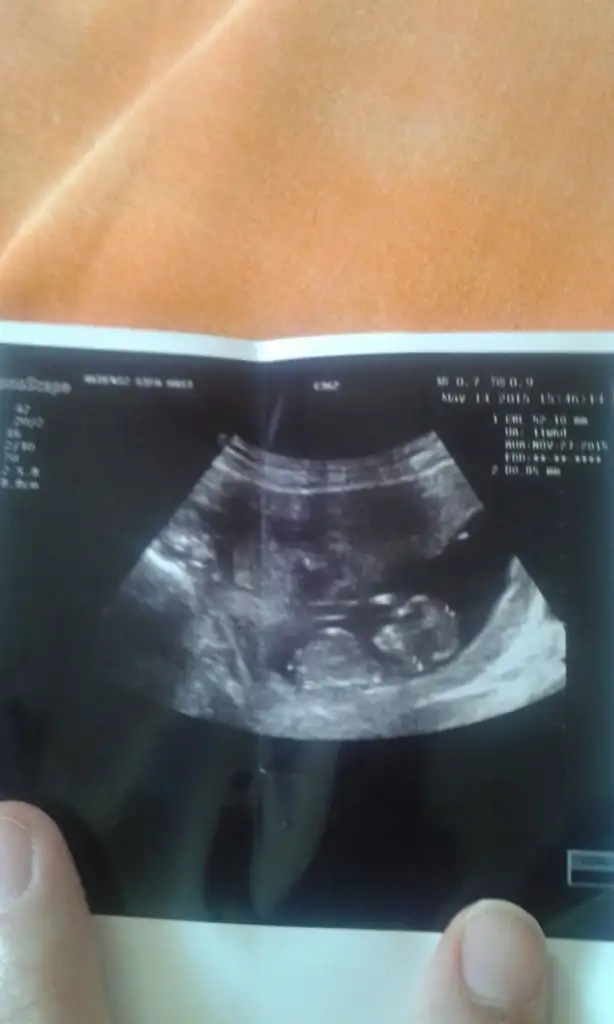

Erkek ilk fotoda bacak arasindan belliEki Görüntüle 1531791 Kizlar tam 13 haftalik sizce cinsiyeti nedir bebegimin:)))

Kiza benzettimKızlar Iyi aksamlar benim içinde yorum yaparsanız çok sevinirim

Kiz.. cikinti yok. Gayet kiz profili var bu bebekte :)) ben %90 diyorum. Ama tabi en kesin doktorun soylerKızlar Merhaba,

Cinsiyet tahmini yapabilir misiniz?

teşekkür ederim umarim. haftaya belli olurCanım seninki kıza benziyor sanki